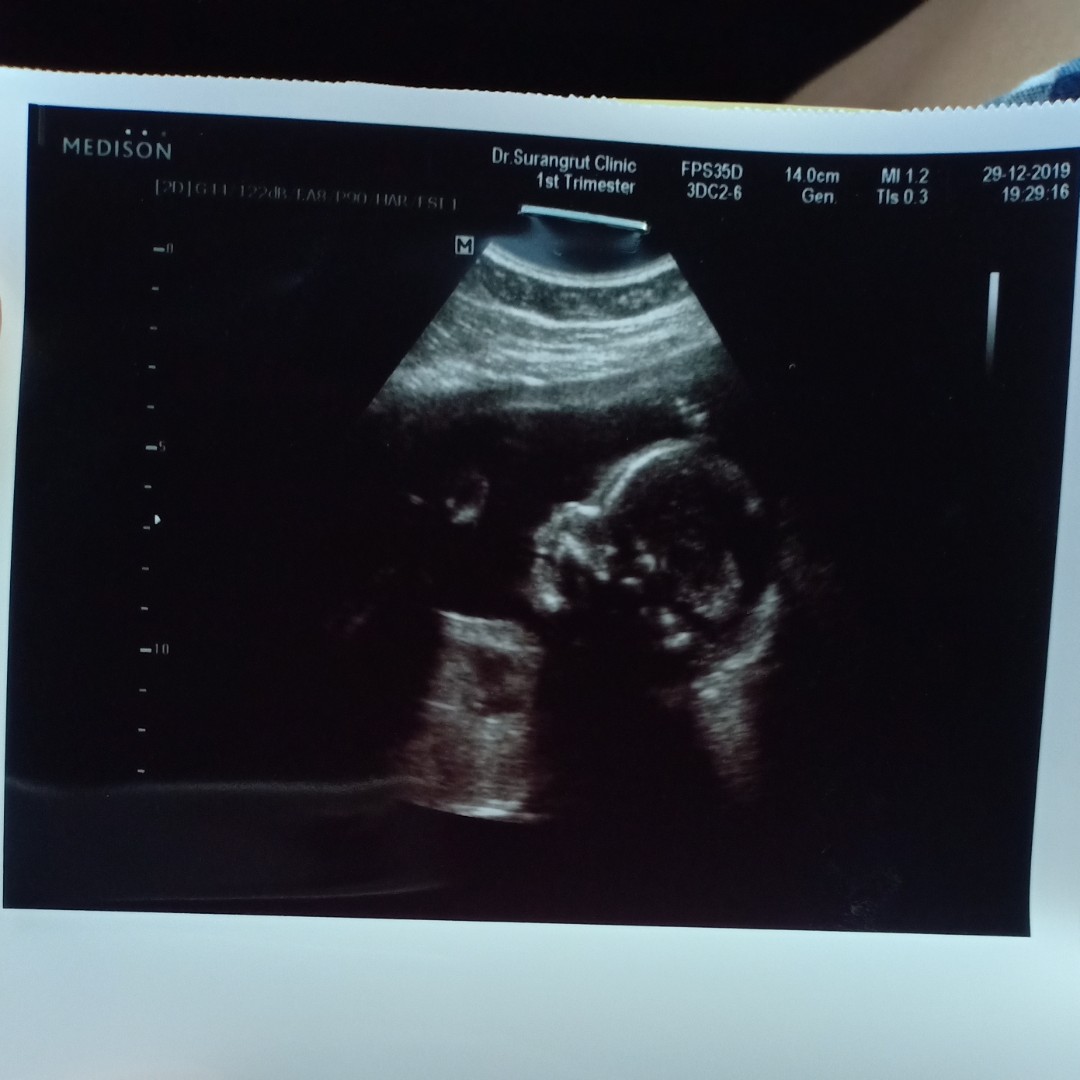

แอบโด่งนิดนึงค่ะ

รอดูตอนคลอด555